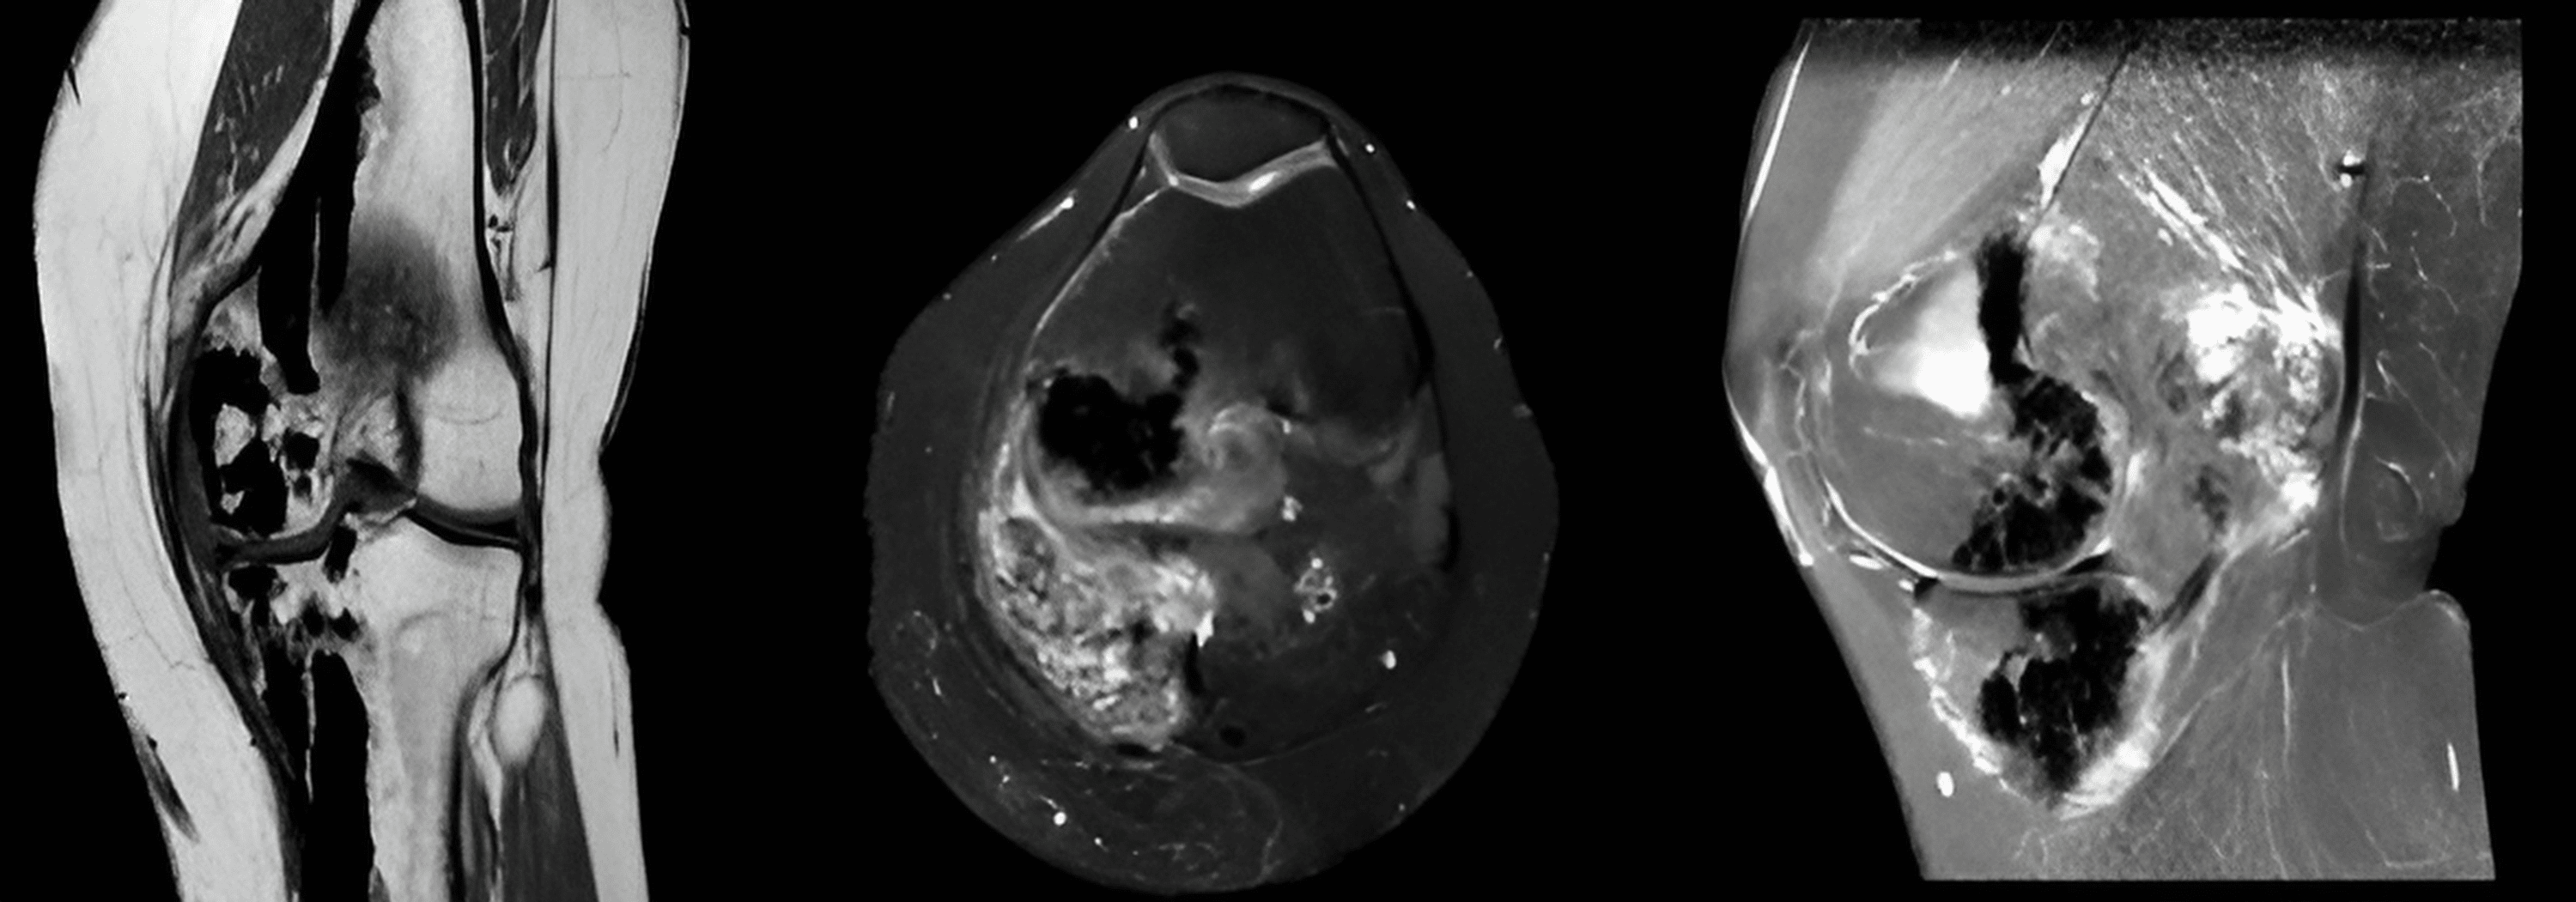

Figure 3 from BuschkeOllendorff Syndrome A Rare Cause of Unilateral Buschke-Ollendorff Mim #166700) is a rare, inherited, autosomal dominant disorder with high. It is a rare disorder of. It is also known as. Specifically, the condition is characterized by skin. Buschke-Ollendorff.